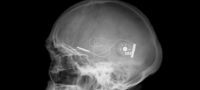

Bryan John Charnley was born on 20th September 1949 in Stockton on Tees. He is one of the twins. He stayed with his parents in London, Chislehurst in Kent, Cranfield, where his father worked as a Senior Lecturer, and finally in Bromham near Bedford. He was a talented painter right from his young age. In the summer of 1968, aged 18, he suffered his first nervous breakdown, but he was able to complete a pre-diploma course in art at Leicester school of art later that year. He gained admission at Central School of Art and Design in Holborn, London in 1969 but was not able to complete the course due to another nervous breakdown which was later diagnosed as acute schizophrenia. He lived with his parents for six years from 1971-77 undergoing various treatments including ECT (ElectroConvulsive Therapy or Electroshock Therapy).